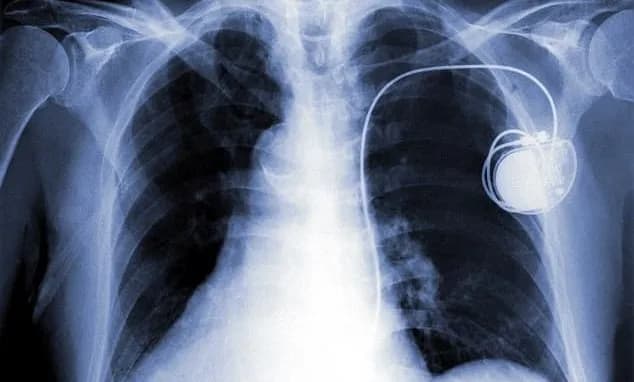

rối loạn nhịp timMáy tạo nhịp timcấy máy tạo nhịpbiến chứng máy tạo nhịpchỉ định máy tạo nhịp

Tổng quan về máy tạo nhịp tim

Máy tạo nhịp tim: Tổng quan, chỉ định và lưu ý

1. Máy tạo nhịp tim là gì?

Tim là một cơ quan vô cùng quan trọng, đóng va...